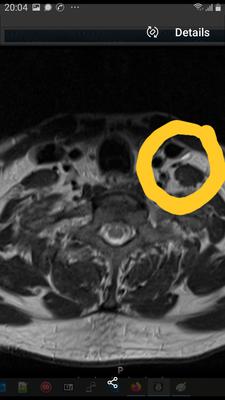

I have a dislocated sternoclavicluar joint, a dislocated first rib at the intercostal joint.

The pain, dizziness, are awful.

They caused 4 embolic strokes.